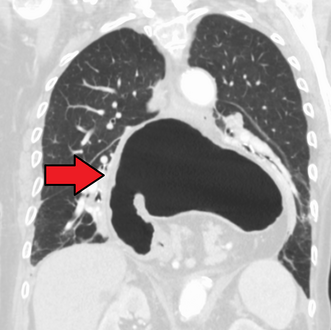

وفي الوقت نفسه، يمكن لقياس الضغط تحديد سلامة حركات المريء ووجود ارتخاء المريء. وتسمح اختبارات الأس الهيدروجيني بالتحليل الكمي لنوبات الارتجاع الحمضي. كما أن التصوير المقطعي المحوسب مفيد في تشخيص مضاعفات الفتق الحجابي مثل الالتواء المعدي، واسترواح الصفاق، واسترواح المنصف.[8]

الفتق الحجابي كما تبينه الأشعة الفوق صوتية.[9]